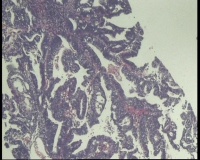

镜下见子宫内膜腺体异型增生,呈乳头状,筛网状排列,细胞核圆形,大小尚均匀,可见少量核分裂像,部分区域鳞化,间质少,部分区域无间质,间质有坏死